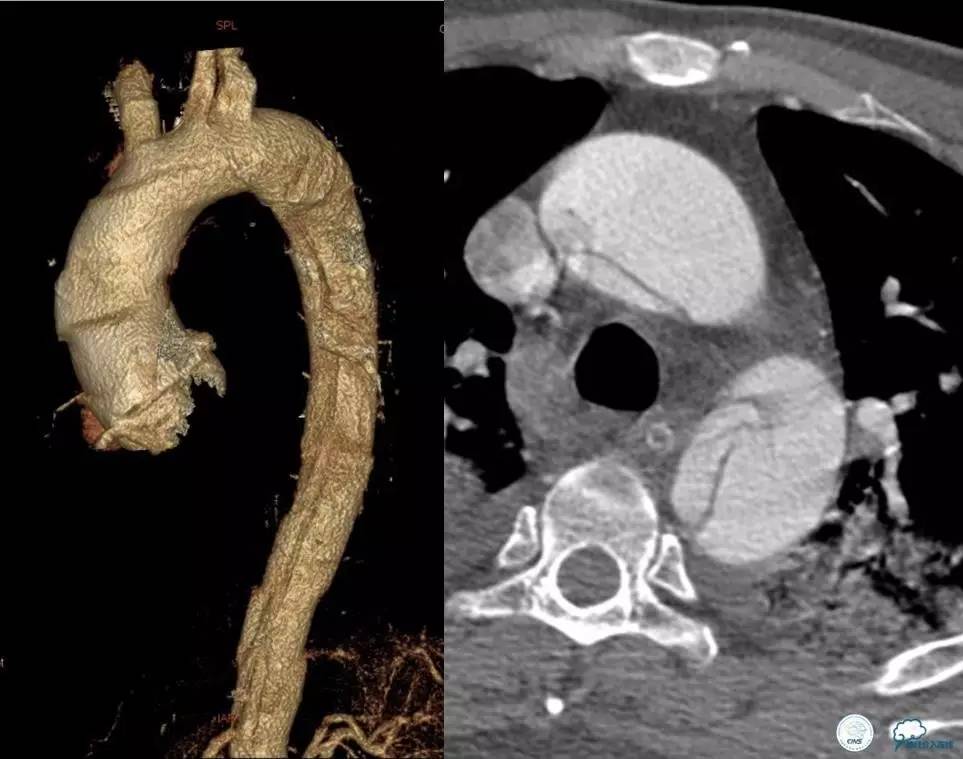

意见:急查主动脉CT。

▼主动脉全程CT

诊断:

主动脉夹层 DeBakey Ⅰ型

短暂性脑缺血发作

急性心肌缺血

急性肾功能不全

急性肠系膜动脉缺血